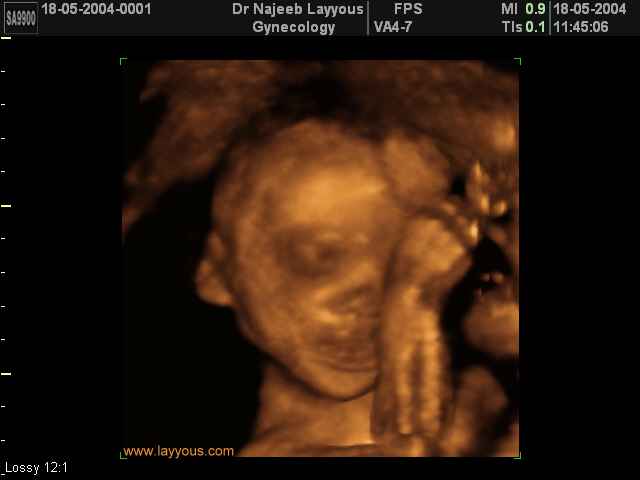

صور لتصرفات الجنين داخل الرحم بجهاز الالتراساوند ثلاثي الأبعاد | الدكتور نجيب ليوس

صور بجهاز الموجات فوق صوتية ثلاثي الأبعاد لتصرفات الجنين داخل الرحم